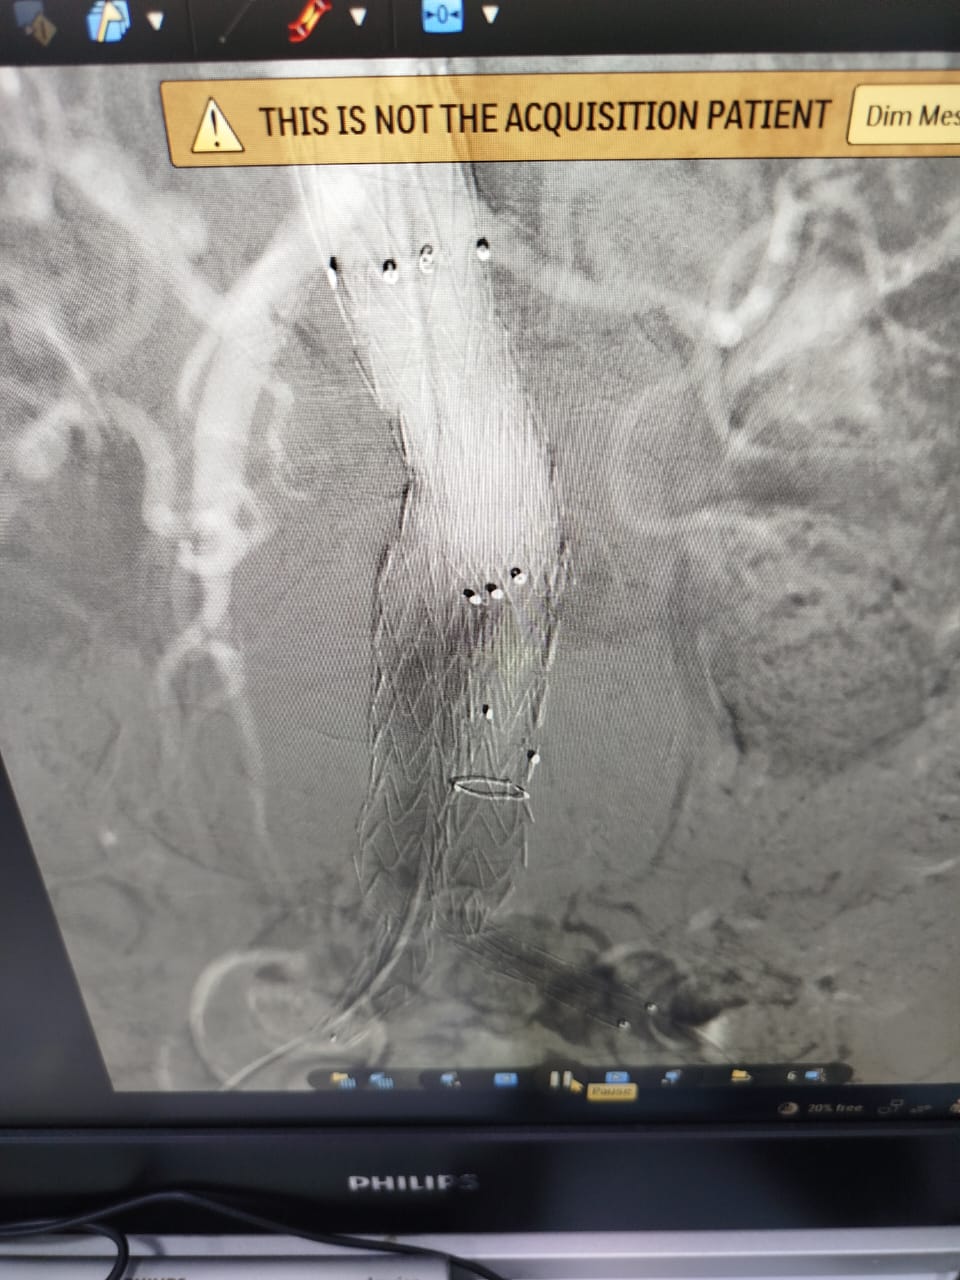

أعلنت الهيئة العامة للرعاية الصحية، عن نجاح أول عملية لعلاج تمدد الشريان الأورطي باستخدام الدعامة المغطاة بتقنية EVAR، لسيدة  مسنة، وذلك داخل مستشفى شرم الشيخ الدولى ، التابع لهيئة الرعاية الصحية بجنوب سيناء.

وأوضح بيان الهيئة، أن المريضة حضرت إلى مستشفى شرم الشيخ الدولى، وبمناظرة الحالة تم اكتشاف وجود تمدد الشريان الرئيسى للقلب (الشريان الأبهر ) للمريضة، وعليه تم عرض الحالة على قسم جراحة الأوعية الدموية، ووجد أن نسبة حدوث انفجار الشريان لهذه المريضة  تتخطى 80%، ووفقًا للبروتوكولات العلاجية أوصى الفريق الطبي المعالج بإجراء عملية لإصلاح تمدد الشريان الأورطي الباطني بتقنية (EVAR) للمريضة.

وتابع البيان: تم إجراء العملية للمنتفعة بنجاح، وبدون أي مضاعفات ، وذلك على يد فريق طبي من أمهر الاستشاريين بمستشفى شرم الشيخ الدولى ضم كل من،  "أ.د احمد رياض ، أ.د شريف حسين" استشاريى جراحة الأوعية الدموية بالمستشفى ، وبمشاركة فريق التخدير برئاسة أ.د إسماعيل عبد الجواد استشاري التخدير ، وبمعاونة فريق التمريض المتميز بمستشفى شرم الشيخ الدولى.

مشيرًا أن منشآت الهيئة، بما في ذلك المستشفيات ومراكز ووحدات صحة الأسرة، تُجهز وفق أعلى المعايير العالمية من حيث الإنشاء والتقنيات الطبية الحديثة، وأوضح أن استخدام تقنيات متطورة مثل تقنية EVAR لعلاج تمدد الشريان الأورطي بدون جراحة، يمثل خطوة نوعية نحو تقليل المخاطر الجراحية وتسريع فترة التعافي، فضلًا عن ضمان العلاج الآمن وفق أحدث الإرشادات  الطبية والبروتوكولات العلاجية الدولية.

جدير بالذكر، أن استخدام الدعامة المغطاة EVAR من أحدث العلاجات المتوفرة عالميًا لعلاج تمدد الشريان الأورطي، وقد تم استحداثها ضمن حزم خدمات منظومة التأمين الصحي الشامل الجديدة ، حيث توفر عدة مزايا منها استخدام نوع تخدير أبسط ويظل المريض مدة أقل تحت تأثير المخدر، مع عدم الاحتياج لنقل دم، وعدم الاحتياج للبقاء في العناية المركزة، سرعة العودة للمنزل بعد يوم واحد من العملية مقارنه بعشرة أيام علي الأقل في حالة الفتح الجراحي.